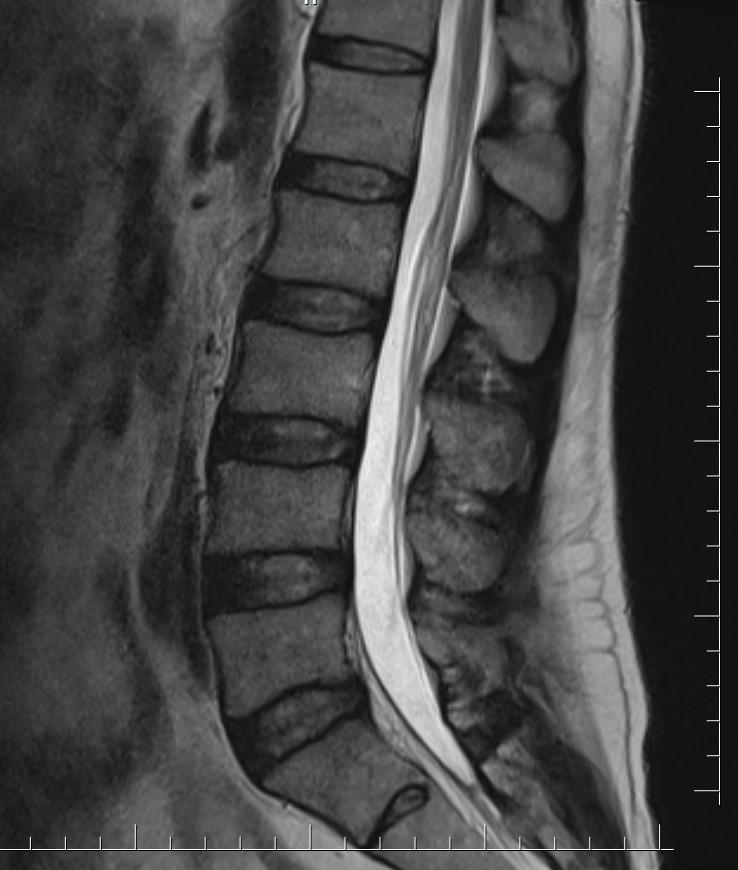

Case of the Week 14 2017 *49-year-old male. What is the most likely diagnosis? Answer Answer: Filum terminale lipoma Kategori:Cases Önceki yazı Case of the Week 17 2017 Sonraki yazı Case of the Week 18 2017